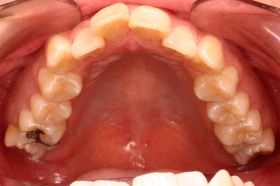

歯の矯正治療 症例ビフォー&アフター

ご覧の症例は出っ歯を矯正治療でキレイにしたケースです。

ご覧の矯正歯科治療の場合は、抜いて矯正歯科

治療していますが東京世田谷矯正歯科センターでは

非抜歯矯正歯科治療をベースにしています。

どうしても抜かないとキレイにならない場合のみ

抜歯して矯正歯科治療しています。